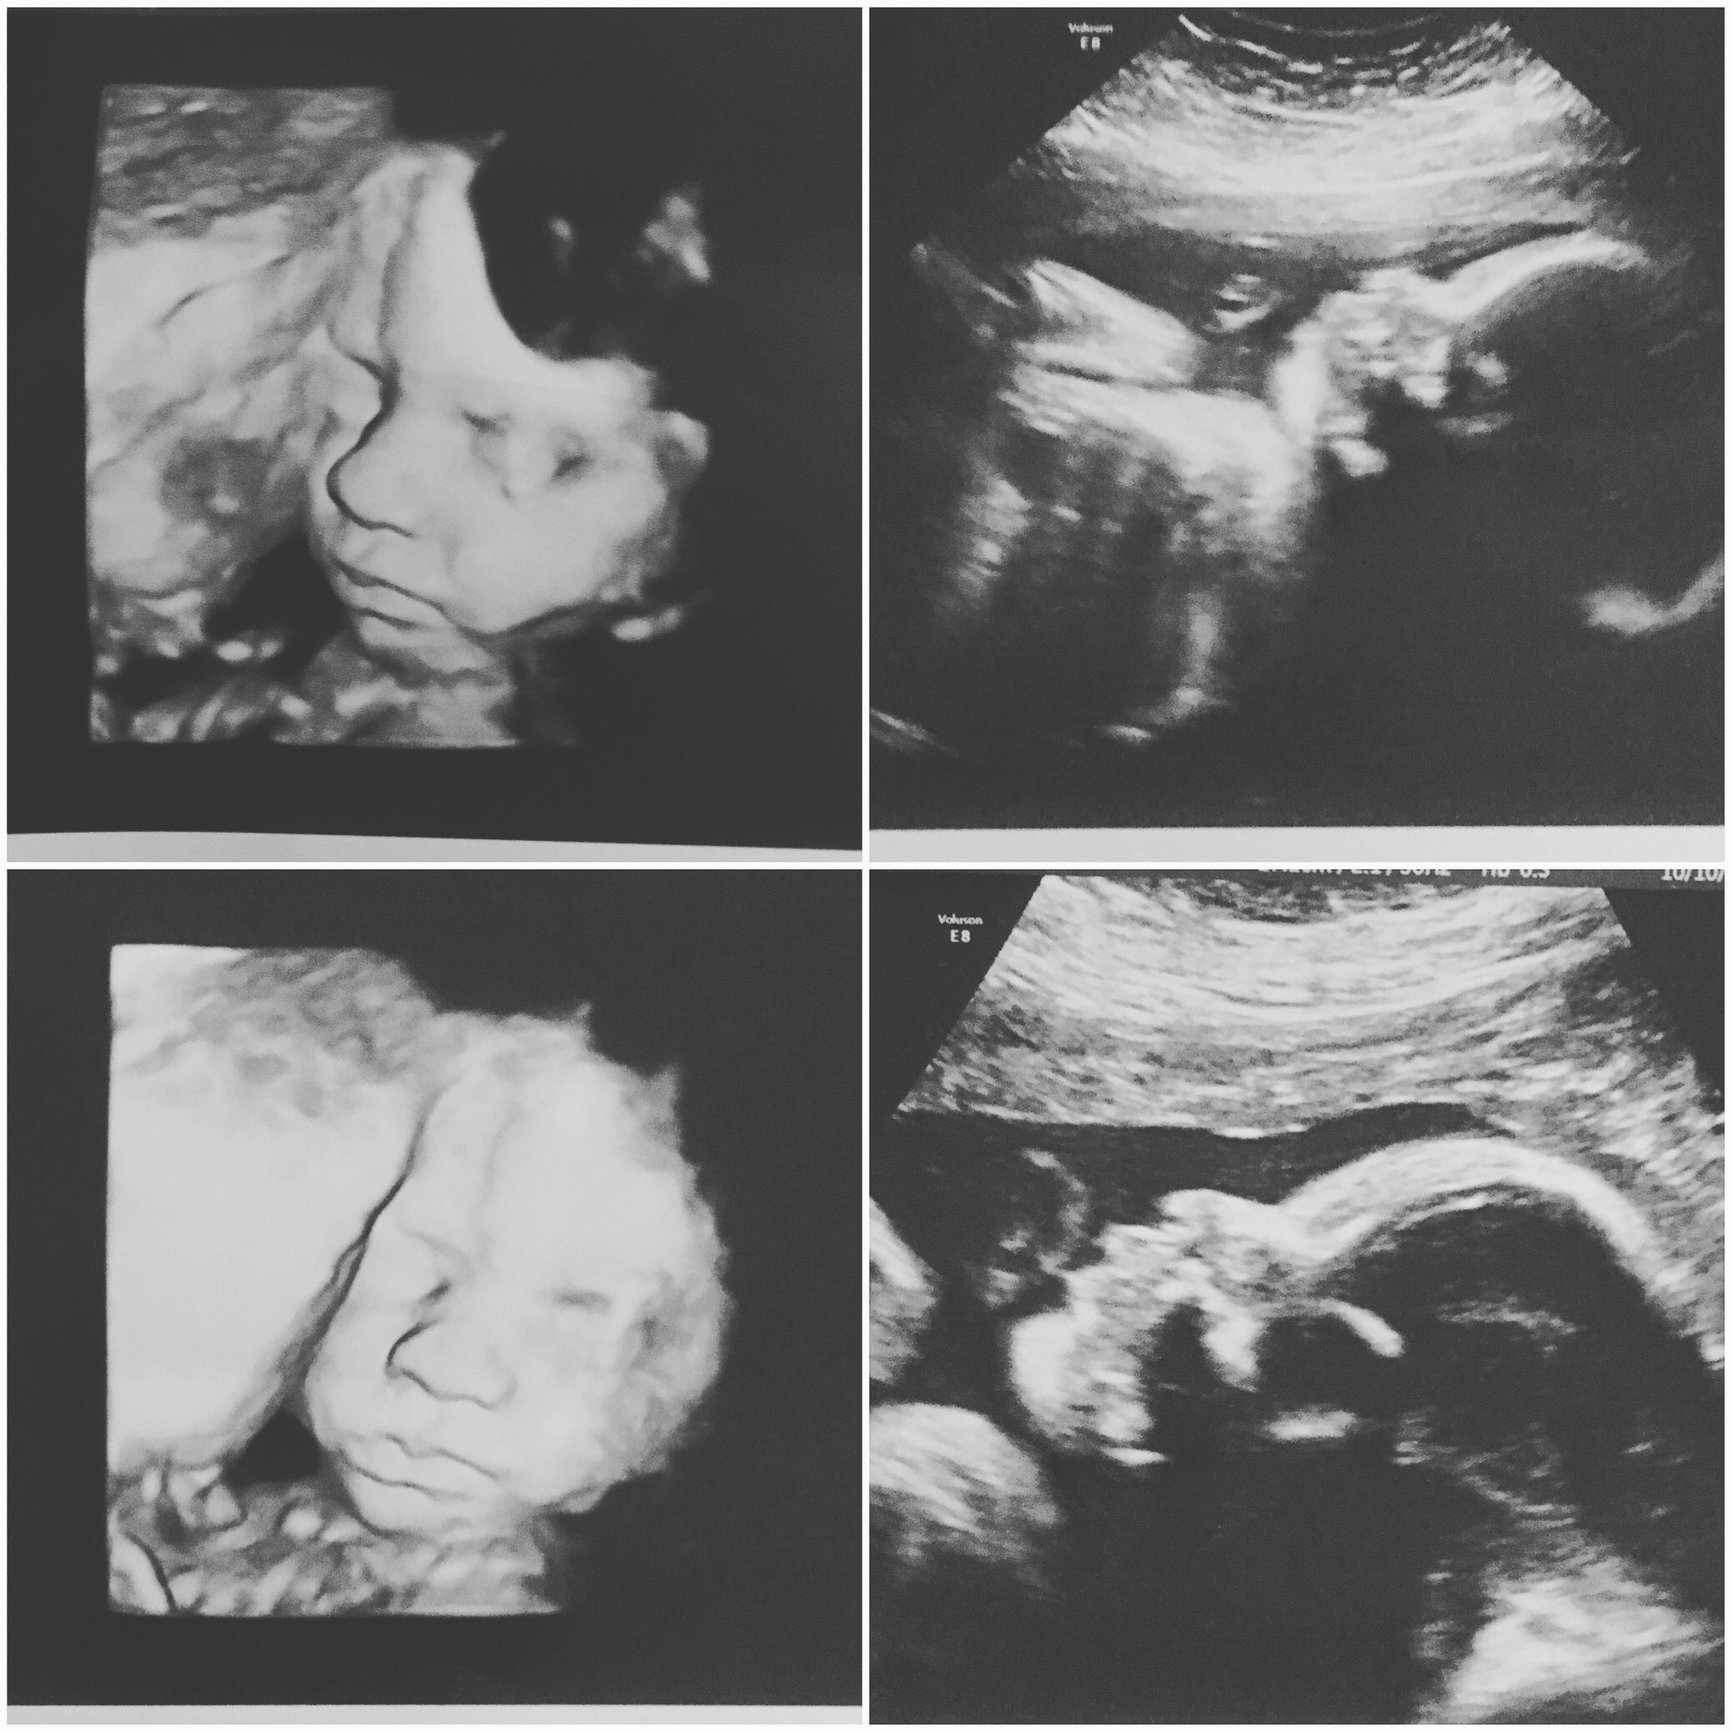

Had my follow up US this morning to check on my marginal previa. It has migrated and, although still a little low, the dr said it's on the right track so no concerns and no more pelvic rest. During the US the tech surprised me with some 3D images and I may or may not have cried like a hormonal baby. BUT COME ON. That smooshy face!!

During the US the tech surprised me with some 3D images and I may or may not have cried like a hormonal baby.

BUT COME ON. That smooshy face!!